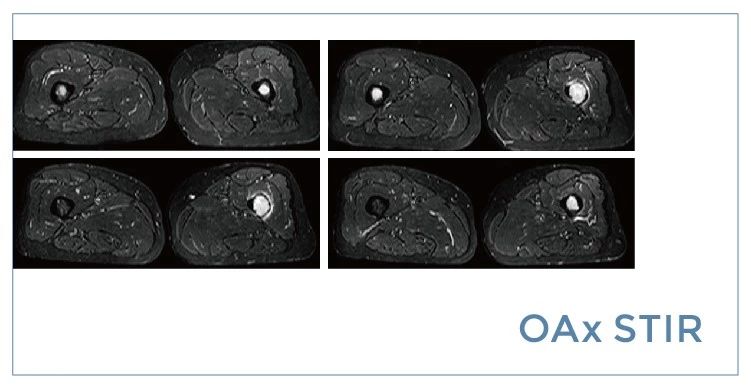

【朗润影像档案】磁共振影像病例分享(编号20190712)